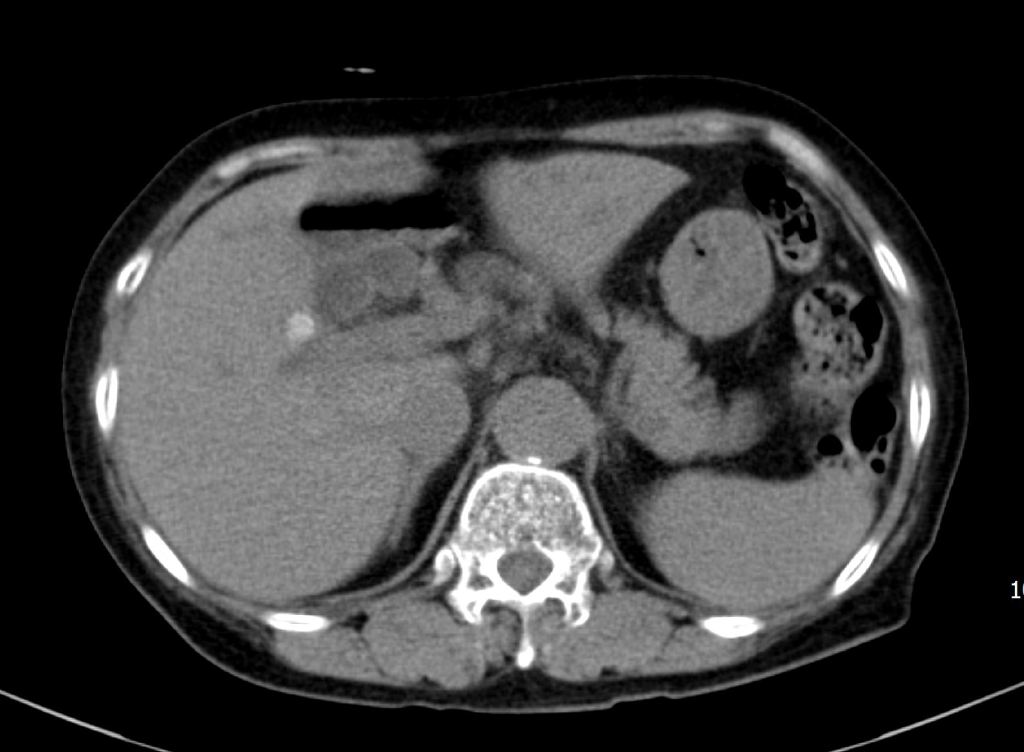

같은 총수담관내 결석을 횡단면 스캔영상으로 확인했습니다. 뚜렷한 후방에코음영을 동반한 결석을 확인할 수 있습니다.